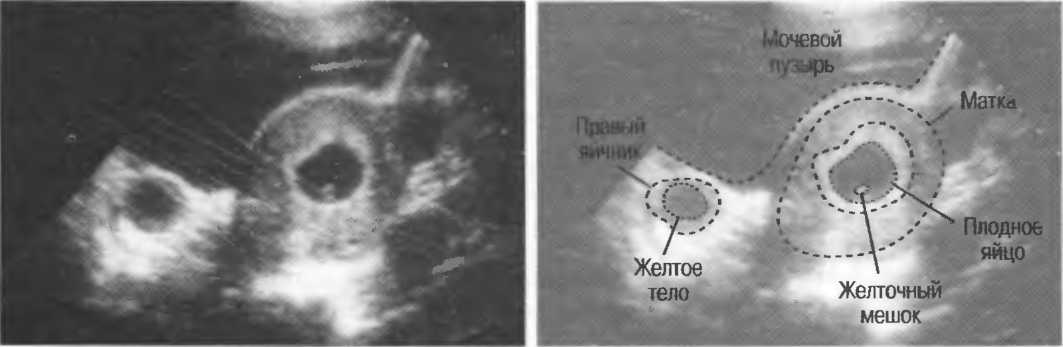

Рис. 12. Фокусировка правильна слева, так как визуализируются детали желточного мешка. Справа детали не видны, так как фокусное расстояние значительно больше.

Рис. 15б. Плодные яйца при анэмбрионии: две жидкостьсодержащие структуры с задним усилением и латеральными тенями.